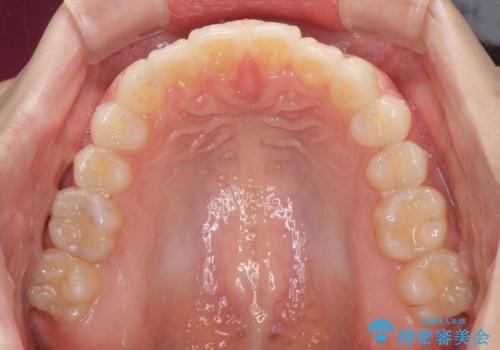

デコボコで飛び出した前歯をきれいに インビザラインによる矯正治療

- デコボコと飛び出した前歯を治したいとのことで来院された患者様です。

ゴムかけを活用して上顎歯列全体を後方移動し、IPR(歯と歯の間を削る)によってデコボコが解消するように設計し、インビザラインにより治療を行うこととしました。

毎日しっかりと装着してくださったので、概ねシミュレーション通りに歯を移動させることができました。

治療前には接触することのなかった上下の前歯が接触するようになり、食事の際前歯でものをかみ切れるようになりました。

気にしていた口元の印象が改善され、患者様には大変満足していただきました。